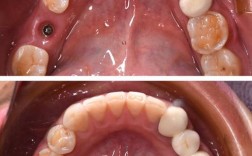

- 上颌骨横向发育不足(牙弓狭窄): 上颌骨左右宽度不够,导致上牙弓狭窄、拥挤,后牙反咬合(俗称“地包天”的一种,指上后牙咬在下后牙里面),影响咀嚼效率和面部对称性。

- 使用扩弓器(快速或慢速)可以轻微扩大上颌牙弓宽度(主要作用于腭中缝的骨缝)。